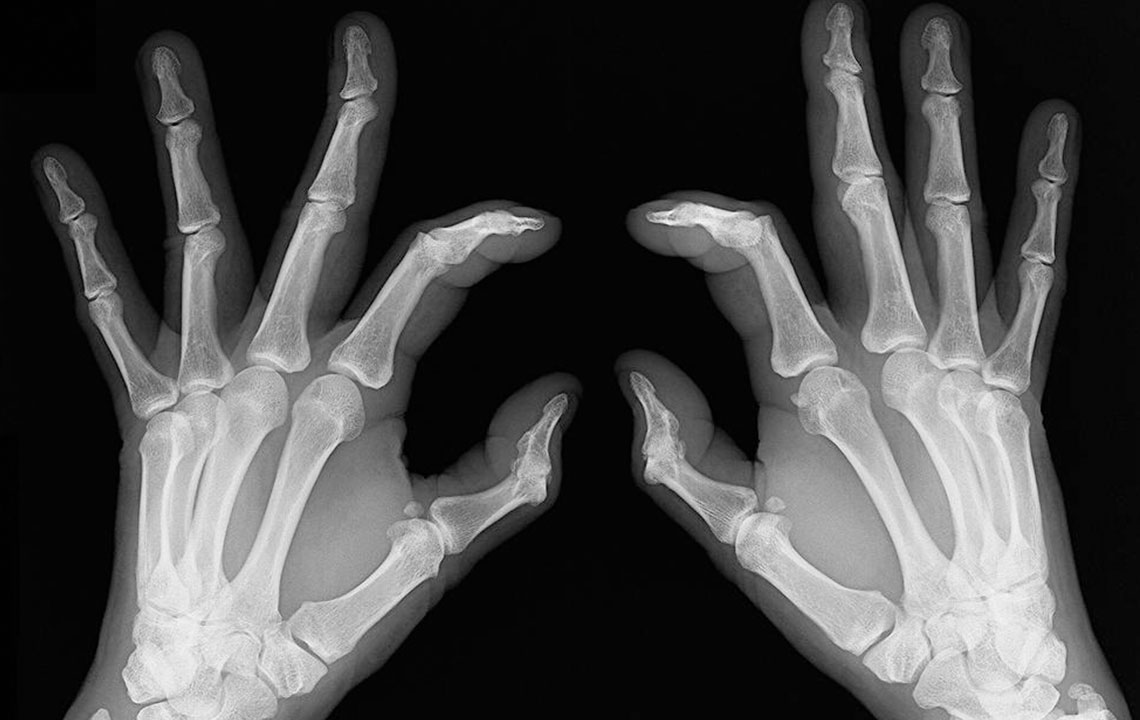

- Bone deformation: Arthritis also attacks the bones and makes them crooked and stiff. Look out for signs of any subtle changes in your joints and test them for pain levels.

Rheumatoid arthritis causes chronic inflammation of joints, which results in joint pains, inflammation and bone deformation. It usually starts slowly with pain in some parts of the body that can come and go in the beginning and then spread within weeks or months. It is better in this day and age to always be aware of your health problems and not to ignore slightest of joint pains.

- Inflammation: Sometimes rheumatoid arthritis symptoms show chronic flare up and can lead to swollen joints and inflammation. They are also symptomatic of lupus, so do consult your doctor before getting yourself treated for rheumatoid arthritis.